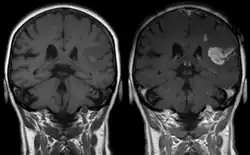

Gadolinium(III) containing MRI contrast agents (often termed simply "gado" or "gad") are the most commonly used for enhancement of vessels in MR angiography or for brain tumor enhancement associated with the degradation of the blood–brain barrier (BBB).[3][4] Over 450 million doses have been administered worldwide from 1988 to 2017.[5] For large vessels such as the aorta and its branches, the dose can be as low as 0.1 mmol/kg of body mass. Higher concentrations are often used for finer vasculature.[6] At much higher concentration, there is more T2 shortening effect of gadolinium, causing gadolinium brightness to be less than surrounding body tissues.[7] However at such concentration, it will cause greater toxicity to bodily tissues.[8]

Gd3+ chelates are hydrophilic and do not readily cross the intact blood–brain barrier. Thus, they are useful in enhancing lesions and tumors where the blood–brain barrier is compromised and the Gd(III) leaks out.[9][lower-alpha 1] In the rest of the body, the Gd3+ initially remains in the circulation but then distributes into the interstitial space or is eliminated by the kidneys.